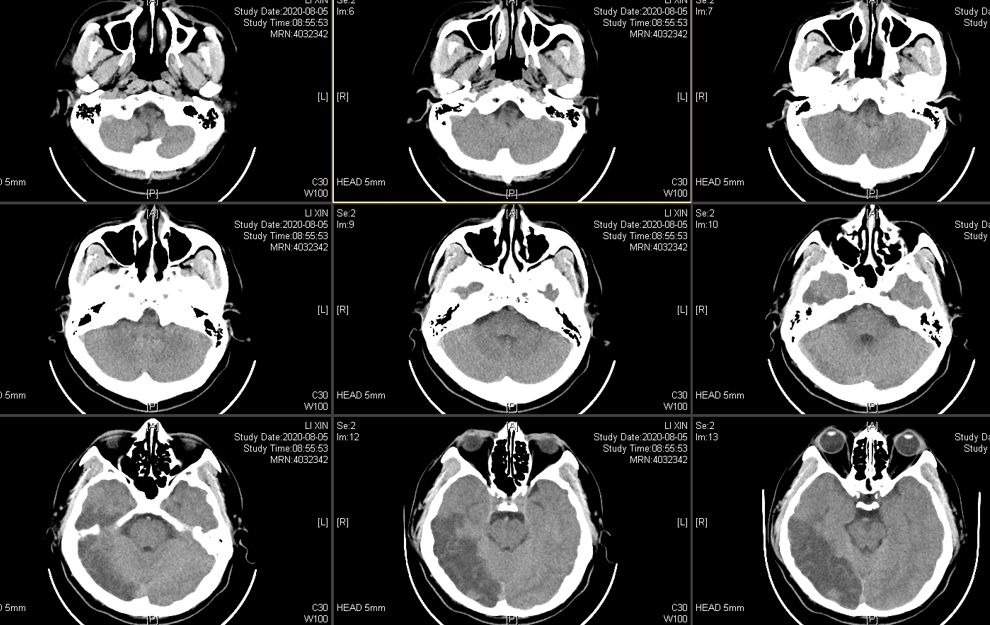

CT显示为右侧颞枕叶脑梗塞,同时累及了大脑中动脉和大脑后动脉分布区。

出血时CT: